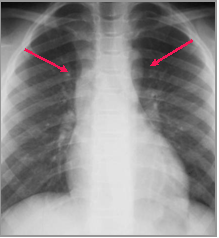

Congenital Aortic Stenosis (10 yo)